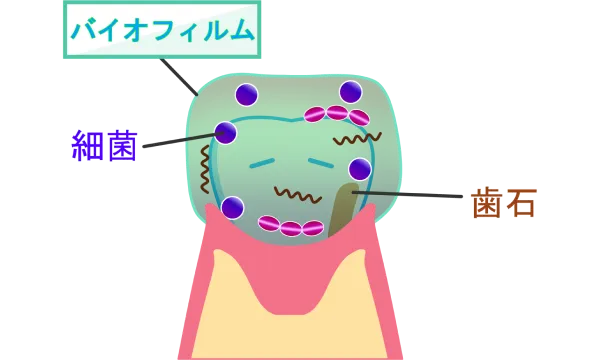

バイオフィルムについて

歯の表面には、歯ブラシをして付着物を取り除いても、しばらくするとたんぱく質の膜が付着します。そこに初めの常在菌が付着し菌塊を形成します。ここに、歯周病菌が付着してさらなる菌塊を作ります。この歯周病菌も常在菌なので、一度感染し定着してしますと駆逐することはできません。 この状態になると、細菌は菌体外重合物質というバリアを作ります。このため、外部と隔離され様々な細菌が集合住宅を作り成熟していきます。この集合住宅がバイオフィルムです。バイオフィルムは3日くらいで完成します。 ただし、この時点で必ず歯周病が発生するとは限りません。その成立には、私たちの抵抗力やバイオフィルムの毒性などが密接に関係するからです。友好関係が崩れないように、健やかなバイオフィルムと暮らすことが重要なのです。